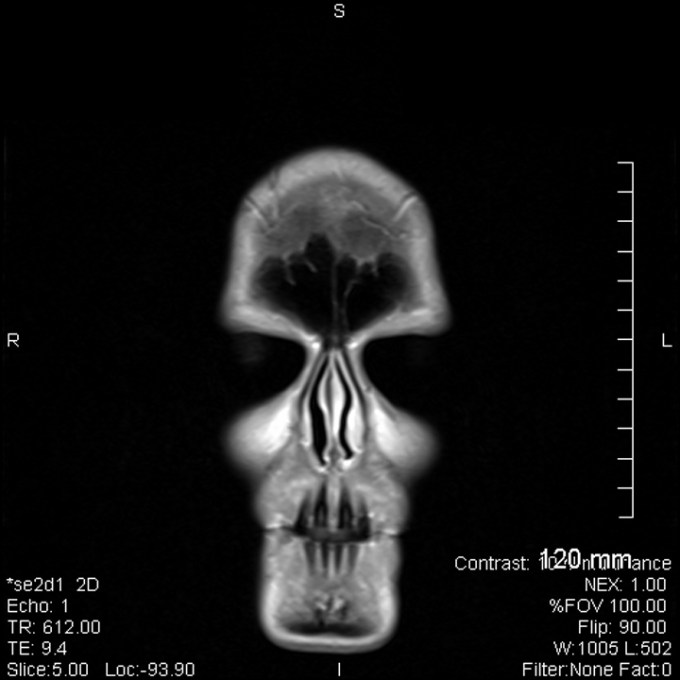

Seriously, now no one can dispute this fact. Today, I have the evidence. I have the scans right here to prove it! So I thought I would share the more interesting slices from my head. Hee hee… I need a copy to take to the specialist next month, so found the jpg images on the disc and loaded them on my computer.

Hey, MS may not be fun, but I’m sure going to have fun with it when I can. We all often get to see an x-ray of an injury, or bones, etc. But rarely do we get to see a scan of our own brain. Now I have… and I think this is awesome!

Oh… and boy, oh, boy… do I have a great idea on something very creative to do with all these images. It will take me a while, but it will most definitely be worth it. But for now, you just get to see the proof that there is something between my ears. And I even included an ear to start out with.